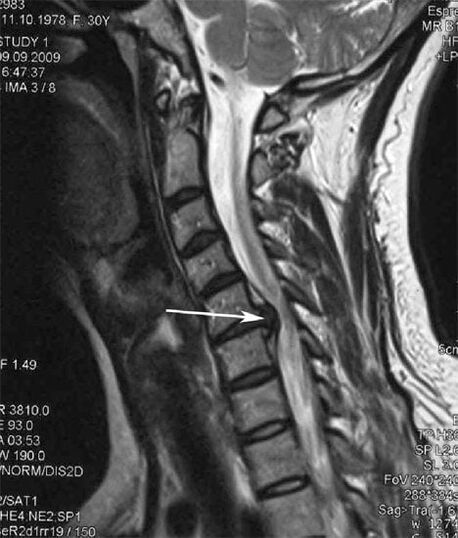

In the initial stages, osteochondrosis is detected using MRI.Later, the pathology can be diagnosed using radiography.On x-rays of the cervical spine, a reduction in the distance between the vertebrae, pathological changes in the facet joints and osteophytosis are noticeable.

Many people complain that they cannot turn their neck because of severe pain when they suddenly lift something heavy.This phenomenon indicates the development of a herniated disc.The cause of pain in the back, neck and upper limbs is pinching of one of the nerve roots exiting the spinal cord.